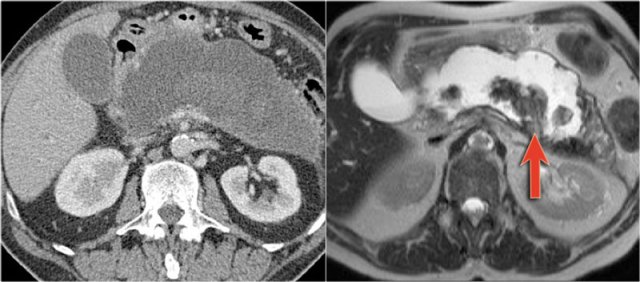

CT images of a 30 year old female with a history of a biliary pancreatitis and cholecystectomy.

She had sudden increased left abdominal pain.

US showed increased size of a cystic lesion, which was diagnosed as a pseudocyst.

The CT however showed a non-lobulated cystic lesion in the pancreatic tail with internal enhancing septation without connection to the pancreatic duct (fig).

Continue with the MRI...

The T1W-image post gadolinium better depicts the internal septations.

Pancreatic tail resection revealed a 14 cm mucinous cystadenoma including ovarian stroma.